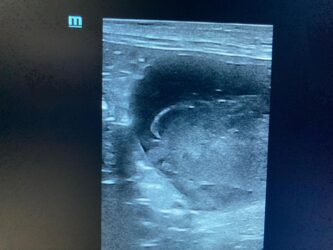

Dimitri, CV, 9.6kg, 11j, MC, bijgeruis 4/6 waarvoor hij vetmedin krijgt en opgevolgd wordt door cardioloog:

21/08/2025: Bij buurtcollega aangeboden voor hematurie. Plast vlot, op’t einde bloed te zien. Mevr. kookt zelf voor hem. Echo gehad + UOZ (geen idee hoe dit werd gecollecteerd) gedaan. Veel bloed in de…